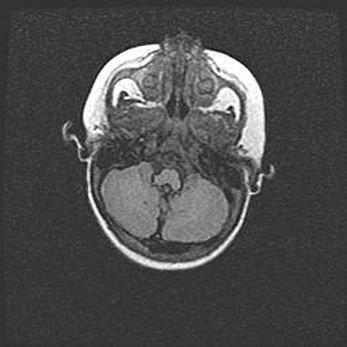

Мальформация Денди-Уокера. Киста задней черепной ямки.

Агенезия мозолистого тела.

Возраст: 2,5 месяца

Вес: 2420 г

Пол: женский

Окружность головы: 37 см

Срок гестации: 32 недели

Мальформация Денди—Уокера — редкий вид патологии ЦНС, представляющий собой врожденный порок развития каудального отдела ствола и червя мозжечка, ведущий к неполному раскрытию срединной (Мажанди) и латеральных (Лушка) апертур IV желудочка мозга. Для этогно синдрома характерна триада симптомов: гипотрофия червя мозжечка и/или полушарий мозжечка, кисты задней черепной ямки, гидроцефалия различной степени. В 70% случаев порок сочетается и с другими аномалиями головного мозга, в частности с агенезией мозолистого тела.